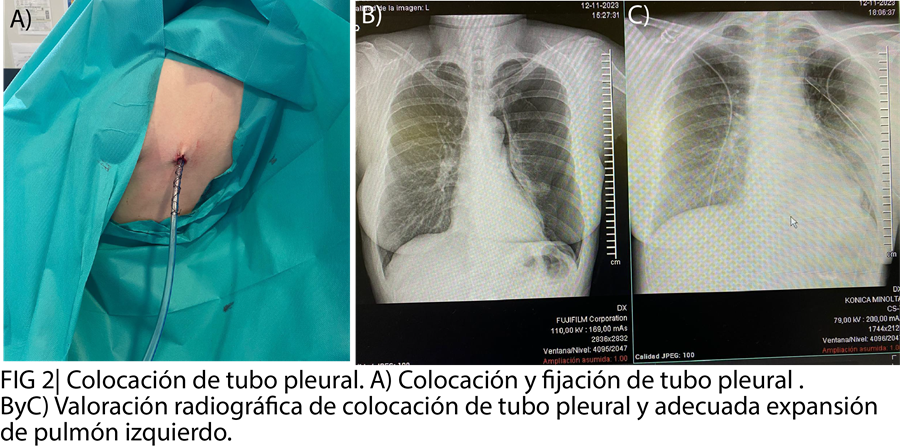

El tratamiento del neumotórax traumático incluyó drenaje torácico guiado por ecografía para reexpandir el pulmón. Se priorizó la analgesia adecuada y la monitorización clínica y radiológica. Plan: seguimiento de la expansión pulmonar y prevención de complicaciones. Ingreso a cargo del servicio de cirugía.

Se trata de una mujer de 46 años con dolor costal, sin disnea, ni repercusión ventilatoria al momento de su llegada pero que mediante ecografía a pie de cama se reveló un neumotórax oculto (signo de código de barras). La paciente requirió drenaje torácico ecoasistido logrando expansión pulmonar.

En este caso, la ecografía clínica permitió identificar hallazgos clave: ausencia de deslizamiento pleural, presencia de líneas B, signo de código de barras y ausencia de pulso pulmón. Aunque no se observó el pulso pulmón, que tiene menor sensibilidad, se confirmó el diagnóstico mediante radiografía de tórax, evidenciando fractura costal y neumotórax traumático izquierdo. La colocación de un tubo de tórax ecoasistido permitió la expansión parcial del pulmón y facilitó un manejo seguro, con ingreso hospitalario para seguimiento y monitorización.